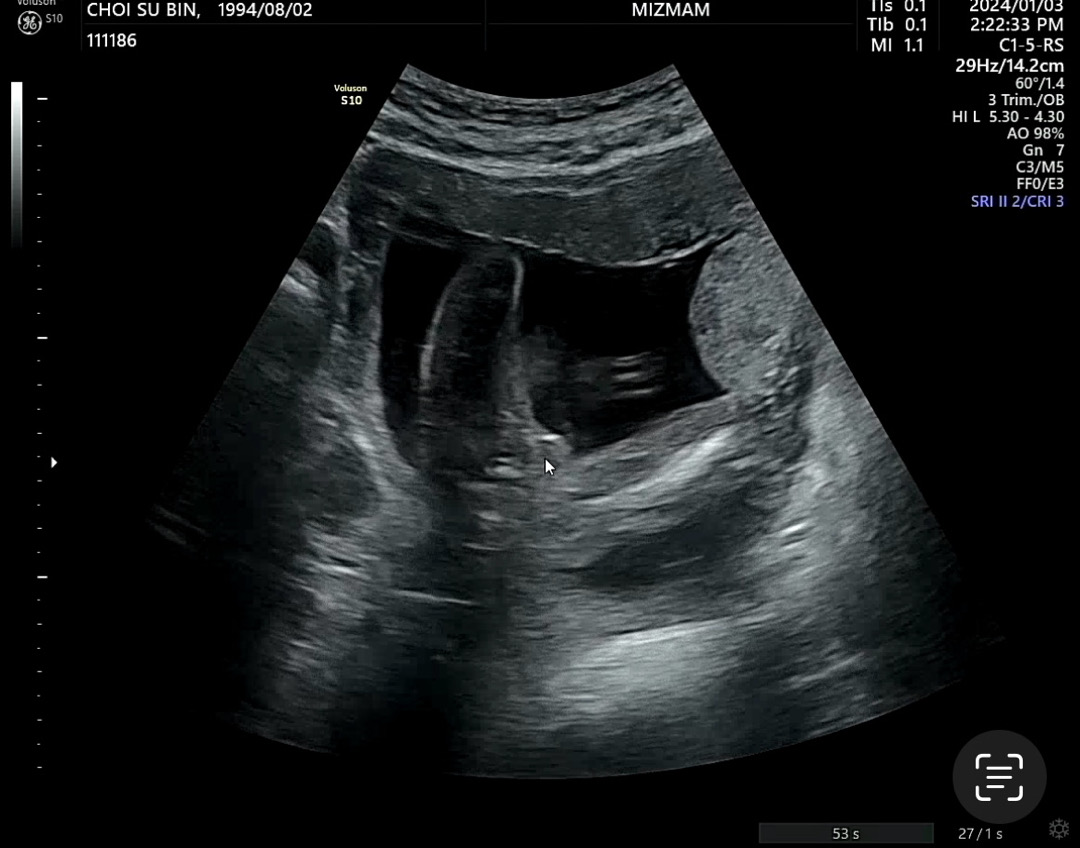

우리 아가 20주 되도록..

성별 안 보여쥬더니 드디어 보여줬는데 선생님이 아들이래요.. 근데 저는 소중이가 안보여서요 마우스 커서 있는 부분이 소중이같은데 다들 보기에 어때보이나요?

아들맞아욥!!! 여자애기는 매끈하다고 했어용 ㅎㅎㅎ